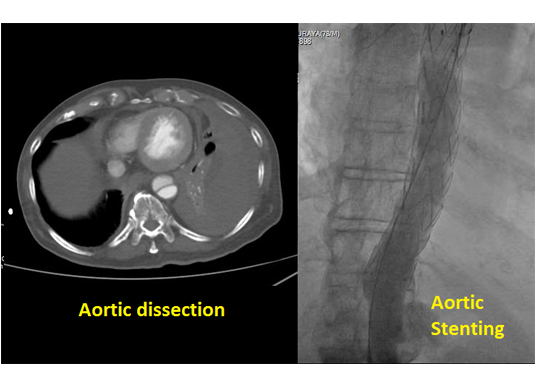

Aorta is the large main artery that carries blood from the heart to all the parts of the body. Aortic aneurysm is a condition where its lumen is over dilated with increased tendency for a fatal rupture. We place a covered stent (almost resembles a flexible hose pipe) through this dilated segment thereby giving it additional support and normal size. In few patients even if aorta is of normal caliber its wall could be diseased and may perforate (aortic dissection). This hole can also be closed by reinforcing its wall with a covered stent.